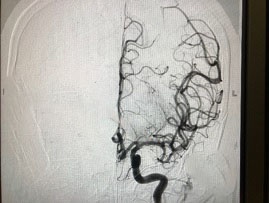

Từ kết quả khám lâm sàng và các xét nghiệm chẩn đoán hình ảnh hiện đại (CT/MRI/MRA), chị Hoa được chẩn đoán nhồi máu não tối cấp do tắc hoàn toàn động mạch não giữa trái. Đây là bệnh tiên lượng nặng, nguy cơ tử vong và tàn phế cao.

Các chuyên gia hàng đầu về đột quỵ tại khu vực miền Trung gồm BS Nguyễn Thái Trí - Trưởng khoa cấp cứu và TS.BS Tôn Thất Trí Dũng - Trưởng khoa Khám bệnh - Nội khoa, Bệnh viện Vinmec Đà Nẵng nhận định, cần thực hiện ngay các biện pháp tái thông mạch máu tái tưới máu não. Không để lãng phí phút giây nào, các bác sĩ đồng thời thực hiện 2 kỹ thuật cấp cứu là làm tan cục máu đông bằng thuốc và can thiệp lấy huyết khối qua đường động mạch.

Hình ảnh chụp mạch máu của chị Hoa bị tắc trước và sau khi được các bác sĩ Vinmec Đà Nẵng can thiệp. |

Kết quả, mạch máu của người bệnh được thông lại sau 40 phút nhập viện và dưới 6 giờ từ khi đột quỵ. Sau can thiệp, tình trạng của bệnh nhân cải thiện rõ rệt. Chị Hoa cử động tốt chân tay bên phải, tỉnh táo, nói và trả lời chính xác tuy chưa được tròn chữ.